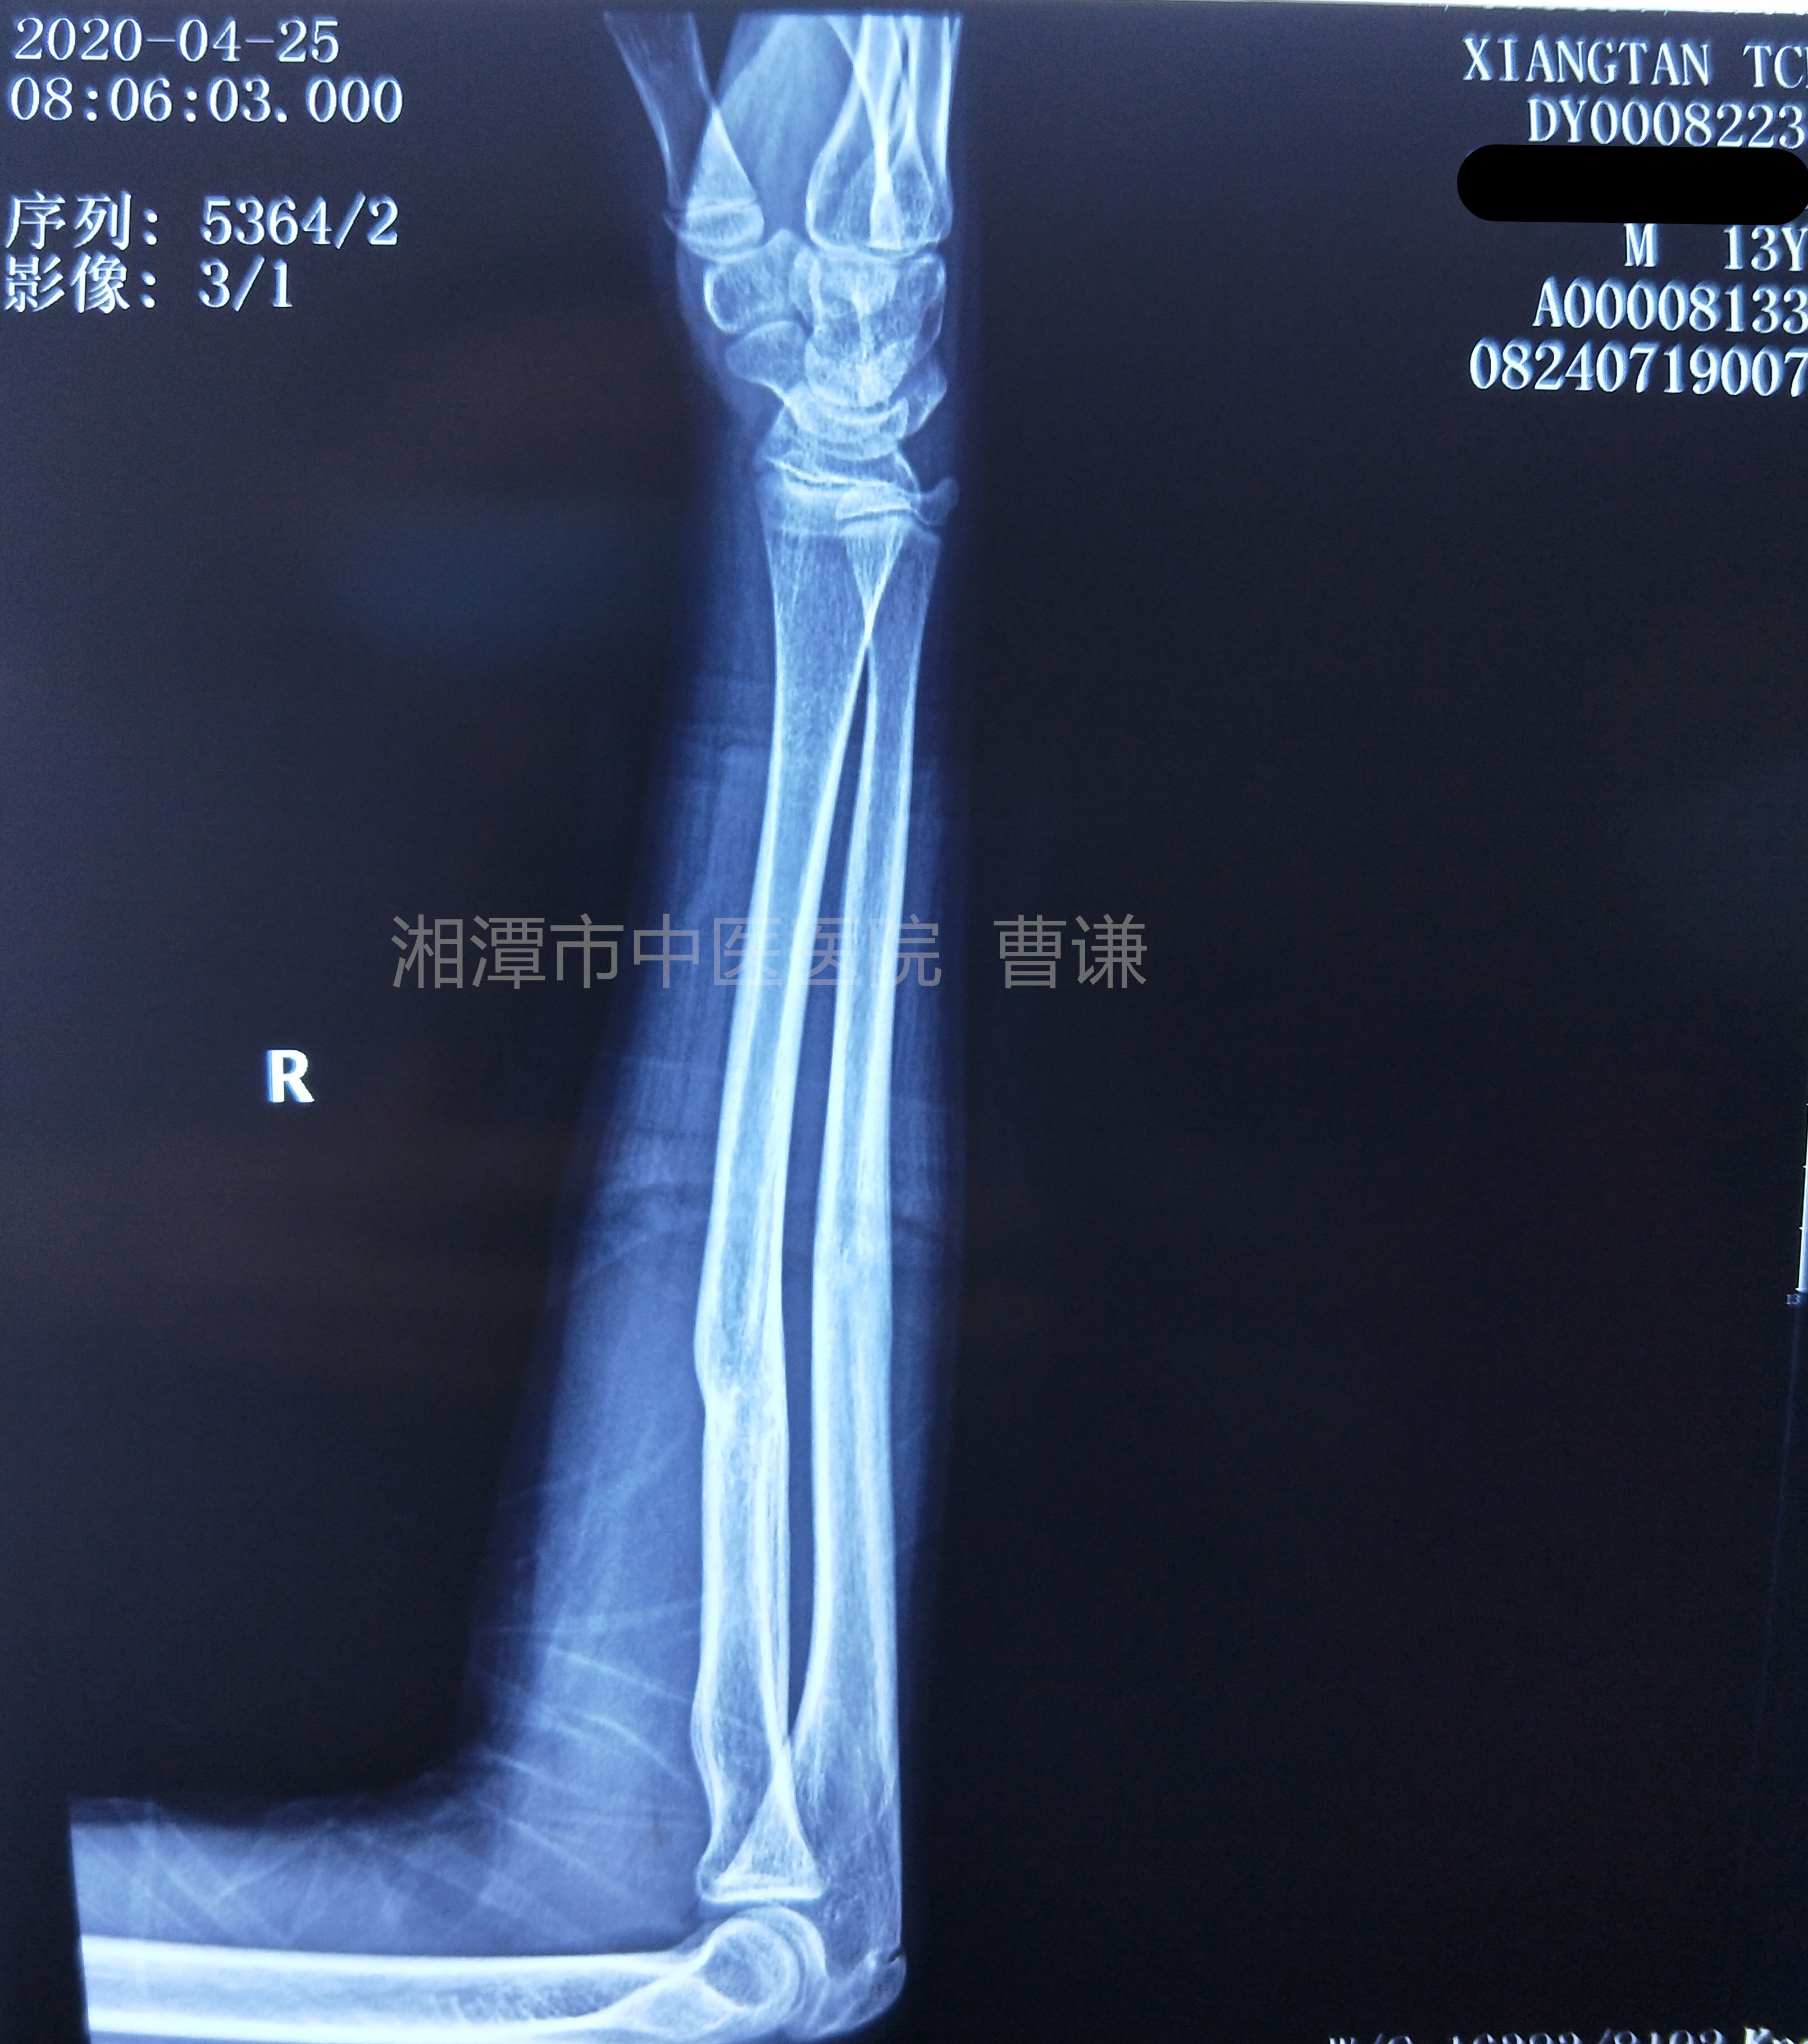

固定一个月后拍片复查见骨痂生长,拆除直角托板,开始肘关节屈伸功能锻炼。

伤后一个半月拍片复查,拆除外固定夹板。